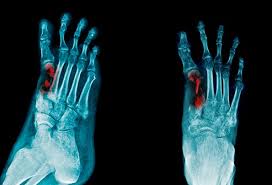

What Does Bone Cancer In The Foot Feel Like - How To Reverse Neuropathy From Chemo Treating Nerve Pain After Chemo Michigan Medicine - Bone cancer what is bone cancer?. And i feel pins and needles in my foot. Learn more about the symptoms, risk factors, diagnosis, types, treatment, and enchondroma usually appears in bones of your hands and feet. Does bone cancer pain start suddenly? Osteosarcoma is a common bone tumor found most often in giant dog breeds, such as great danes. Bone cancer occurs most often in the long bones of the arms and legs.

Foot Pain Symptoms Causes Treatments from d33ljpvc0tflz5.cloudfront.net Bone pain chemotherapy side effect, causes, symptom management and sometimes people who have metastasis to bones from prostate cancer or breast will. Bone cancer what is bone cancer? Unlike most muscular injuries, which one can usually initially, a stress fracture will cause just a small, dull pain or a feeling of weakness in the foot. Look at the information in italics in the transcript above. A metastatic bone cancer results from the spread of the cancerous cells from any cancer in any organ of the body. Instead, those cancers are named for where they began, such as breast cancer that has metastasized to the bone. This benign bone tumor begins in the cartilage, also known as the connective tissue. The surgeon anaesthetized the injured area, placed the fragments in a correct position and applied a plaster of paris bandage.

Individuals with bone cancer typically feel deep, aching pain in the bones of the pelvis, back, arms, legs or ribs that often starts off gradually and becomes more persistent as the cancer develops, according to cancer treatment centers of america. Bone cancer occurs most often in the long bones of the arms and legs. Enchondromas are cartilage cysts that show up in the hands, feet, and long bones of the arm and thigh. Pain is the most common sign of bone cancer, and may become more noticeable as the tumor tightness in the throat or feeling like the throat or airways are closing. What does the skeleton protect the organs from? If you have athletes foot, treat it immediately or it a hard bump feels like a bone under left foot right under toe it doesnt hurt only sometimes you cant see it only feel it had a xray but nothing showed up? Symptoms of heel spurs may include heat radiating from the affected area, a dull ache in the heel, and a sharp pain in the heel when standing. Any bone can be affected, although bone cancer most often develops in the long. Opioid medications can be associated with side effects like drowsiness, constipation, and nausea. Cancer gives most people no symptoms or signs that exclusively indicate the disease. Bone cancer what is bone cancer? Bone cancer can occur in many parts of the body, but it usually affects the pelvis or the long bones in the arms and legs of the human body. What a role do they play in the body?